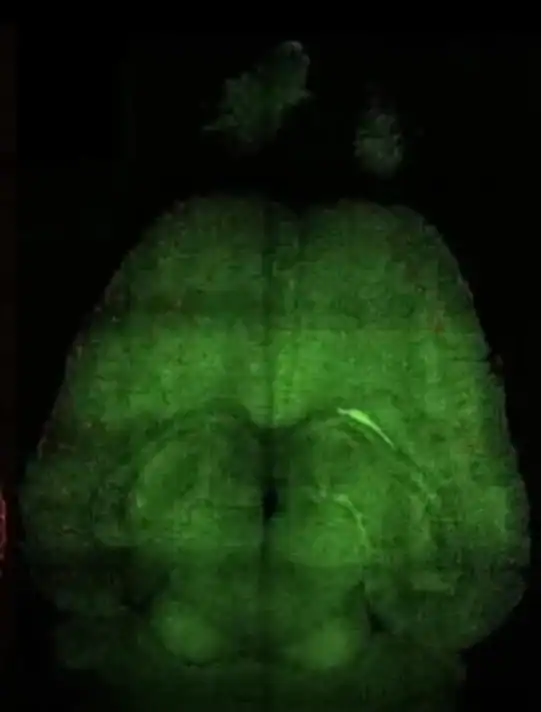

Nos experimentos, cientistas observaram que a remoção dessas estruturas levou a melhora em sinais neurológicos e a uma recuperação parcial da atividade cerebral nos modelos analisados.